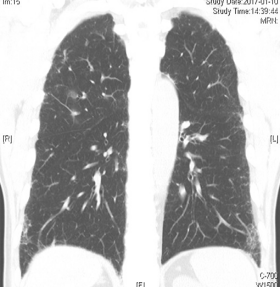

病例:男性,33岁,劳力性呼吸困难4年,加重3月,在治疗之前,我们看到的影像有些磨玻璃影、马赛克征,还有小叶中央型结节,并进行了外科肺活检。患者在从事铸造工作过程中间断接触异氰酸酯。停止工作暴露,并糖皮质激素经过治疗后,病情好转,但停用激素后又出现了肺部弥漫的磨玻璃影,肺功能也有所下降。

图:(从左至右)治疗前、脱离暴露+激素治疗10月、停激素18月